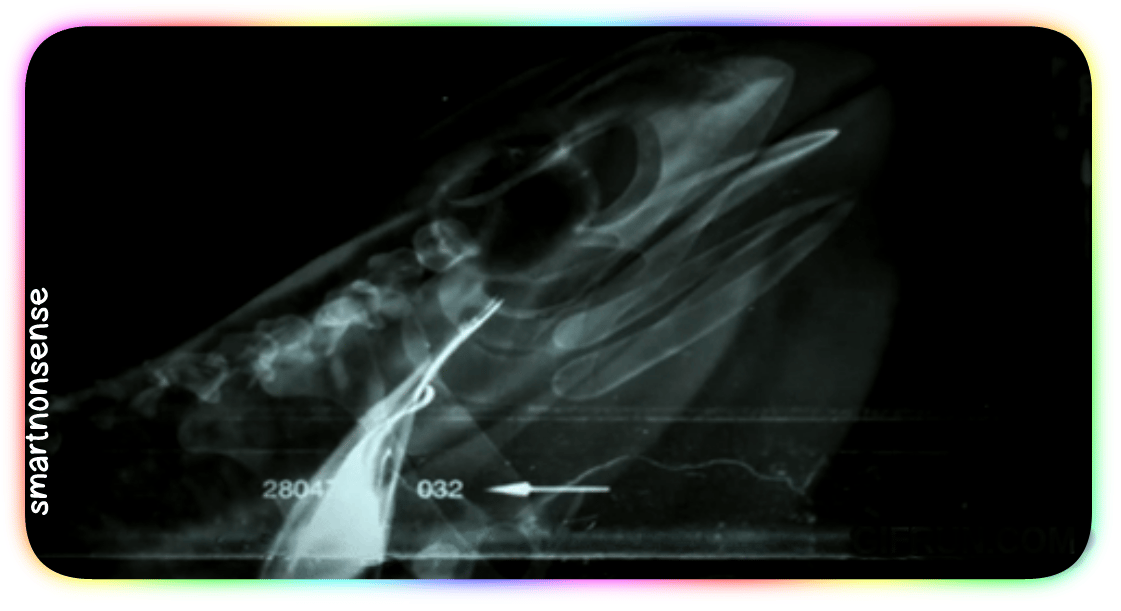

Check out this X-ray:

When you go to swallow that fly, your eyeballs (which – you know – usually just sit in their sockets)

Get PULLED down by muscles

Into your skull!

They press HARD on the roof of your mouth:

Driving that meal straight down your throat!